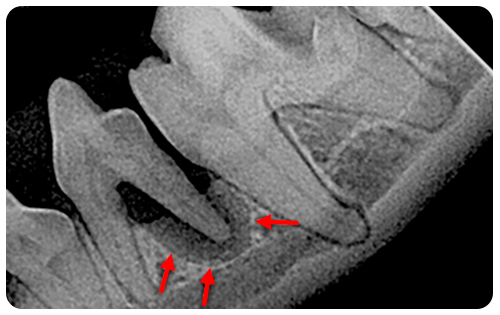

Los perros no pueden decirnos cuándo tienen una enfermedad dental, y algunos nunca muestran dolor, incluso si lo tienen. En muchos casos, las radiografías son la única forma de poder determinar si existe un problema dental y su gravedad. Por ejemplo, en la imagen, los dientes parecen normales, pero la radiografía muestra una pérdida ósea grave debido a una enfermedad periodontal dolorosa (flechas rojas en la imagen de abajo).